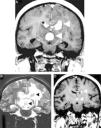

When PCNSL are suspected, corticotherapy should be avoided or discontinued because tumor shrinkage results in radiographic regression in approximately 40% of patients (‘the vanishing tumor’), which is suggestive of PCNSL (Figure 2). The detection of a ‘vanishing tumor’ should not be considered in the diagnosis of PCNSL because sarcoidosis, brain demyelination, acute encephalomyelitis, and other malignancies (more rarely) can exhibit dramatic responses to steroids.3,18

Corticotherapy effects in a primary central nervous system lymphoma. An axial T1 image after intravenous gadolinium administration (A) shows multifocal primary central nervous system lymphoma as deep homogeneous enhanced masses in the corpus callosum, which are adjacent to the third ventricle (arrowheads). A comparative T2-weighted image (B) depicts nodular hypointensity in the lesions with perilesional vasogenic edema (arrowheads). A comparative T1 image after intravenous gadolinium administration (C) was obtained after corticotherapy and demonstrated evident tumor shrinkage (‘vanishing tumors’).